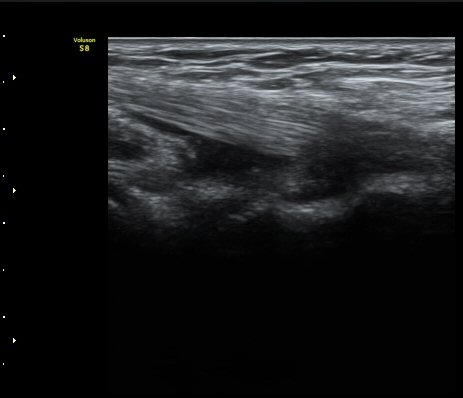

À̵ιڱ٠ÈûÁÙ Á¾´Ü¸é°Ë»ç¿¡¼­ ÈûÁÙÀÌ Àú¿¡ÄÚ°í °üÂûµÇ°í ÈûÁÙ ÁÖº¯ÀÇ ¼ö¾×Àú·ù°¡

¾Ö¸ÅÇÏ°Ô °üÂûµÈ´Ù(±×¸² 7). ŽÃËÀÚ ±ÙÀ§ºÎ¸¦ ÇǺÎÂÊÀ¸·Î ´©¸£´Ï ÈûÁÙÀÌ °í¿¡ÄÚ·Î

°üÂûµÇ°í ¼ö¾×Àú·ùµµ ¶Ñ·ÈÇÏ´Ù(±×¸² 8).